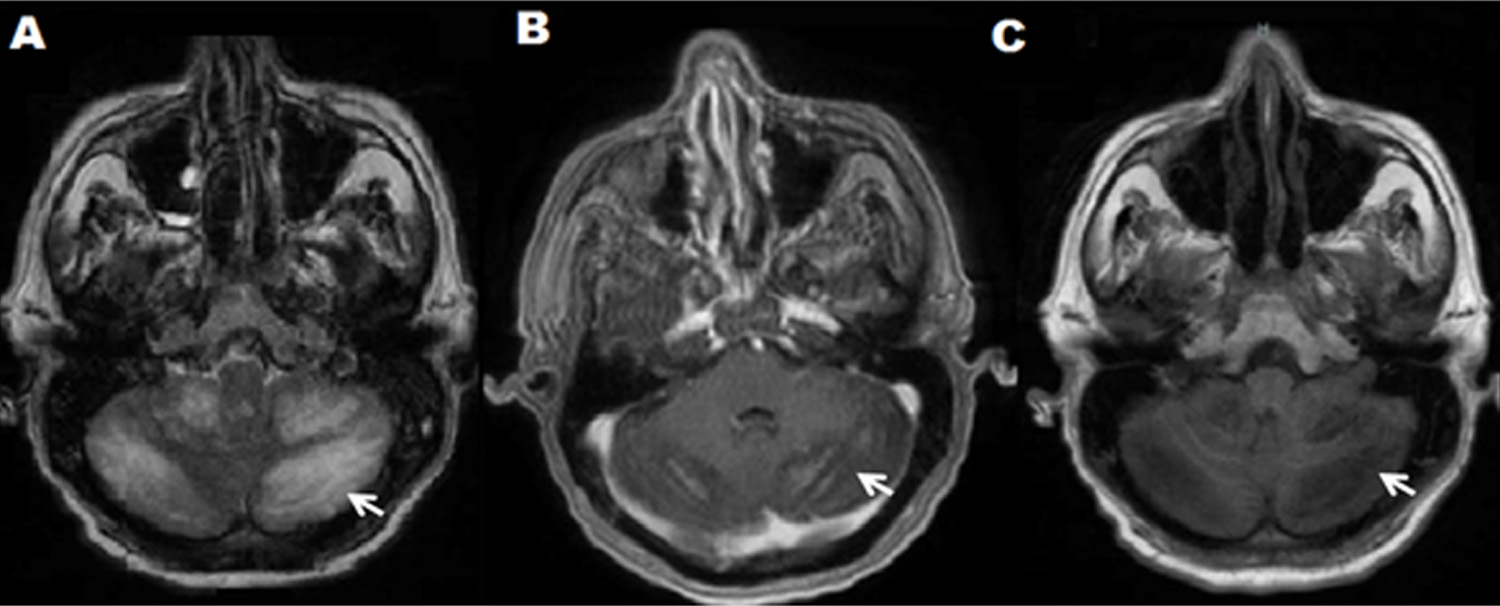

A neurological examination revealed an obscure, confused patient with normal fundoscopy, no signs of endocranial hypertension, nor meningeal, normal force in all four limbs. A determination of Reactive Protein C and Globular Sedimentation Velocity was performed, a hemogram with leukocytosis and neutrophilia. The ELISA test for HIV was negative. With a diagnostic impression of epileptic syndrome, a computerized axial tomography (CT) scan of the brain was requested and showed no signs of endocranial hypertension, expansive lesions, or other relevant lesions. A lumbar puncture was performed demonstrating hypoglycemia and hyperproteinorraquia (Table 1), so it was decided to study as meningitis. On the third day of hospitalization, the patient persisted with altered state of consciousness, and presented dysmetria, dysarthria, dysdiadochokinesia, a positive Stewart-Holmes sign and a right hand drive without nystagmus, nor intentional tremor. For persisting without clinical improvement, another lumbar puncture was performed, which found that he found a high opening pressure, pleocytosis and hypoglycemia. The Chinese ink staining allowed to identify encapsulated blastoconidides compatible with Cryptococcus spp that were confirmed in cultures in blood agar, chocolate and Sabouraud, where C. neoformans var. Grubii NIV in the Laboratory of the National Institute of Health of Colombia. Antifungal therapy with Amphotericin B at 50 mg daily and Fluconazole at 400 mg every 12 hours was initiated, with improved mental status, decreased febrile episodes, headache, ataxia and dysmetria. On the ninth day of hospitalization, the results of the MRI were reported: in the T1 segment diffuse hypointense cerebellar lesion with contrast enhancement without evidence of nodule or abscess; In the T2 Flair sequence, a predominantly right bilateral diffuse hyperintense cerebellar lesion corresponding to inflammatory changes was evidenced. (Fig. 1A, B, C). The definitive diagnosis of Cryptococcal Cerebellum was made. The same antifungal therapy was continued for one week until epileptic status was reported for a period of approximately 12 min and died.